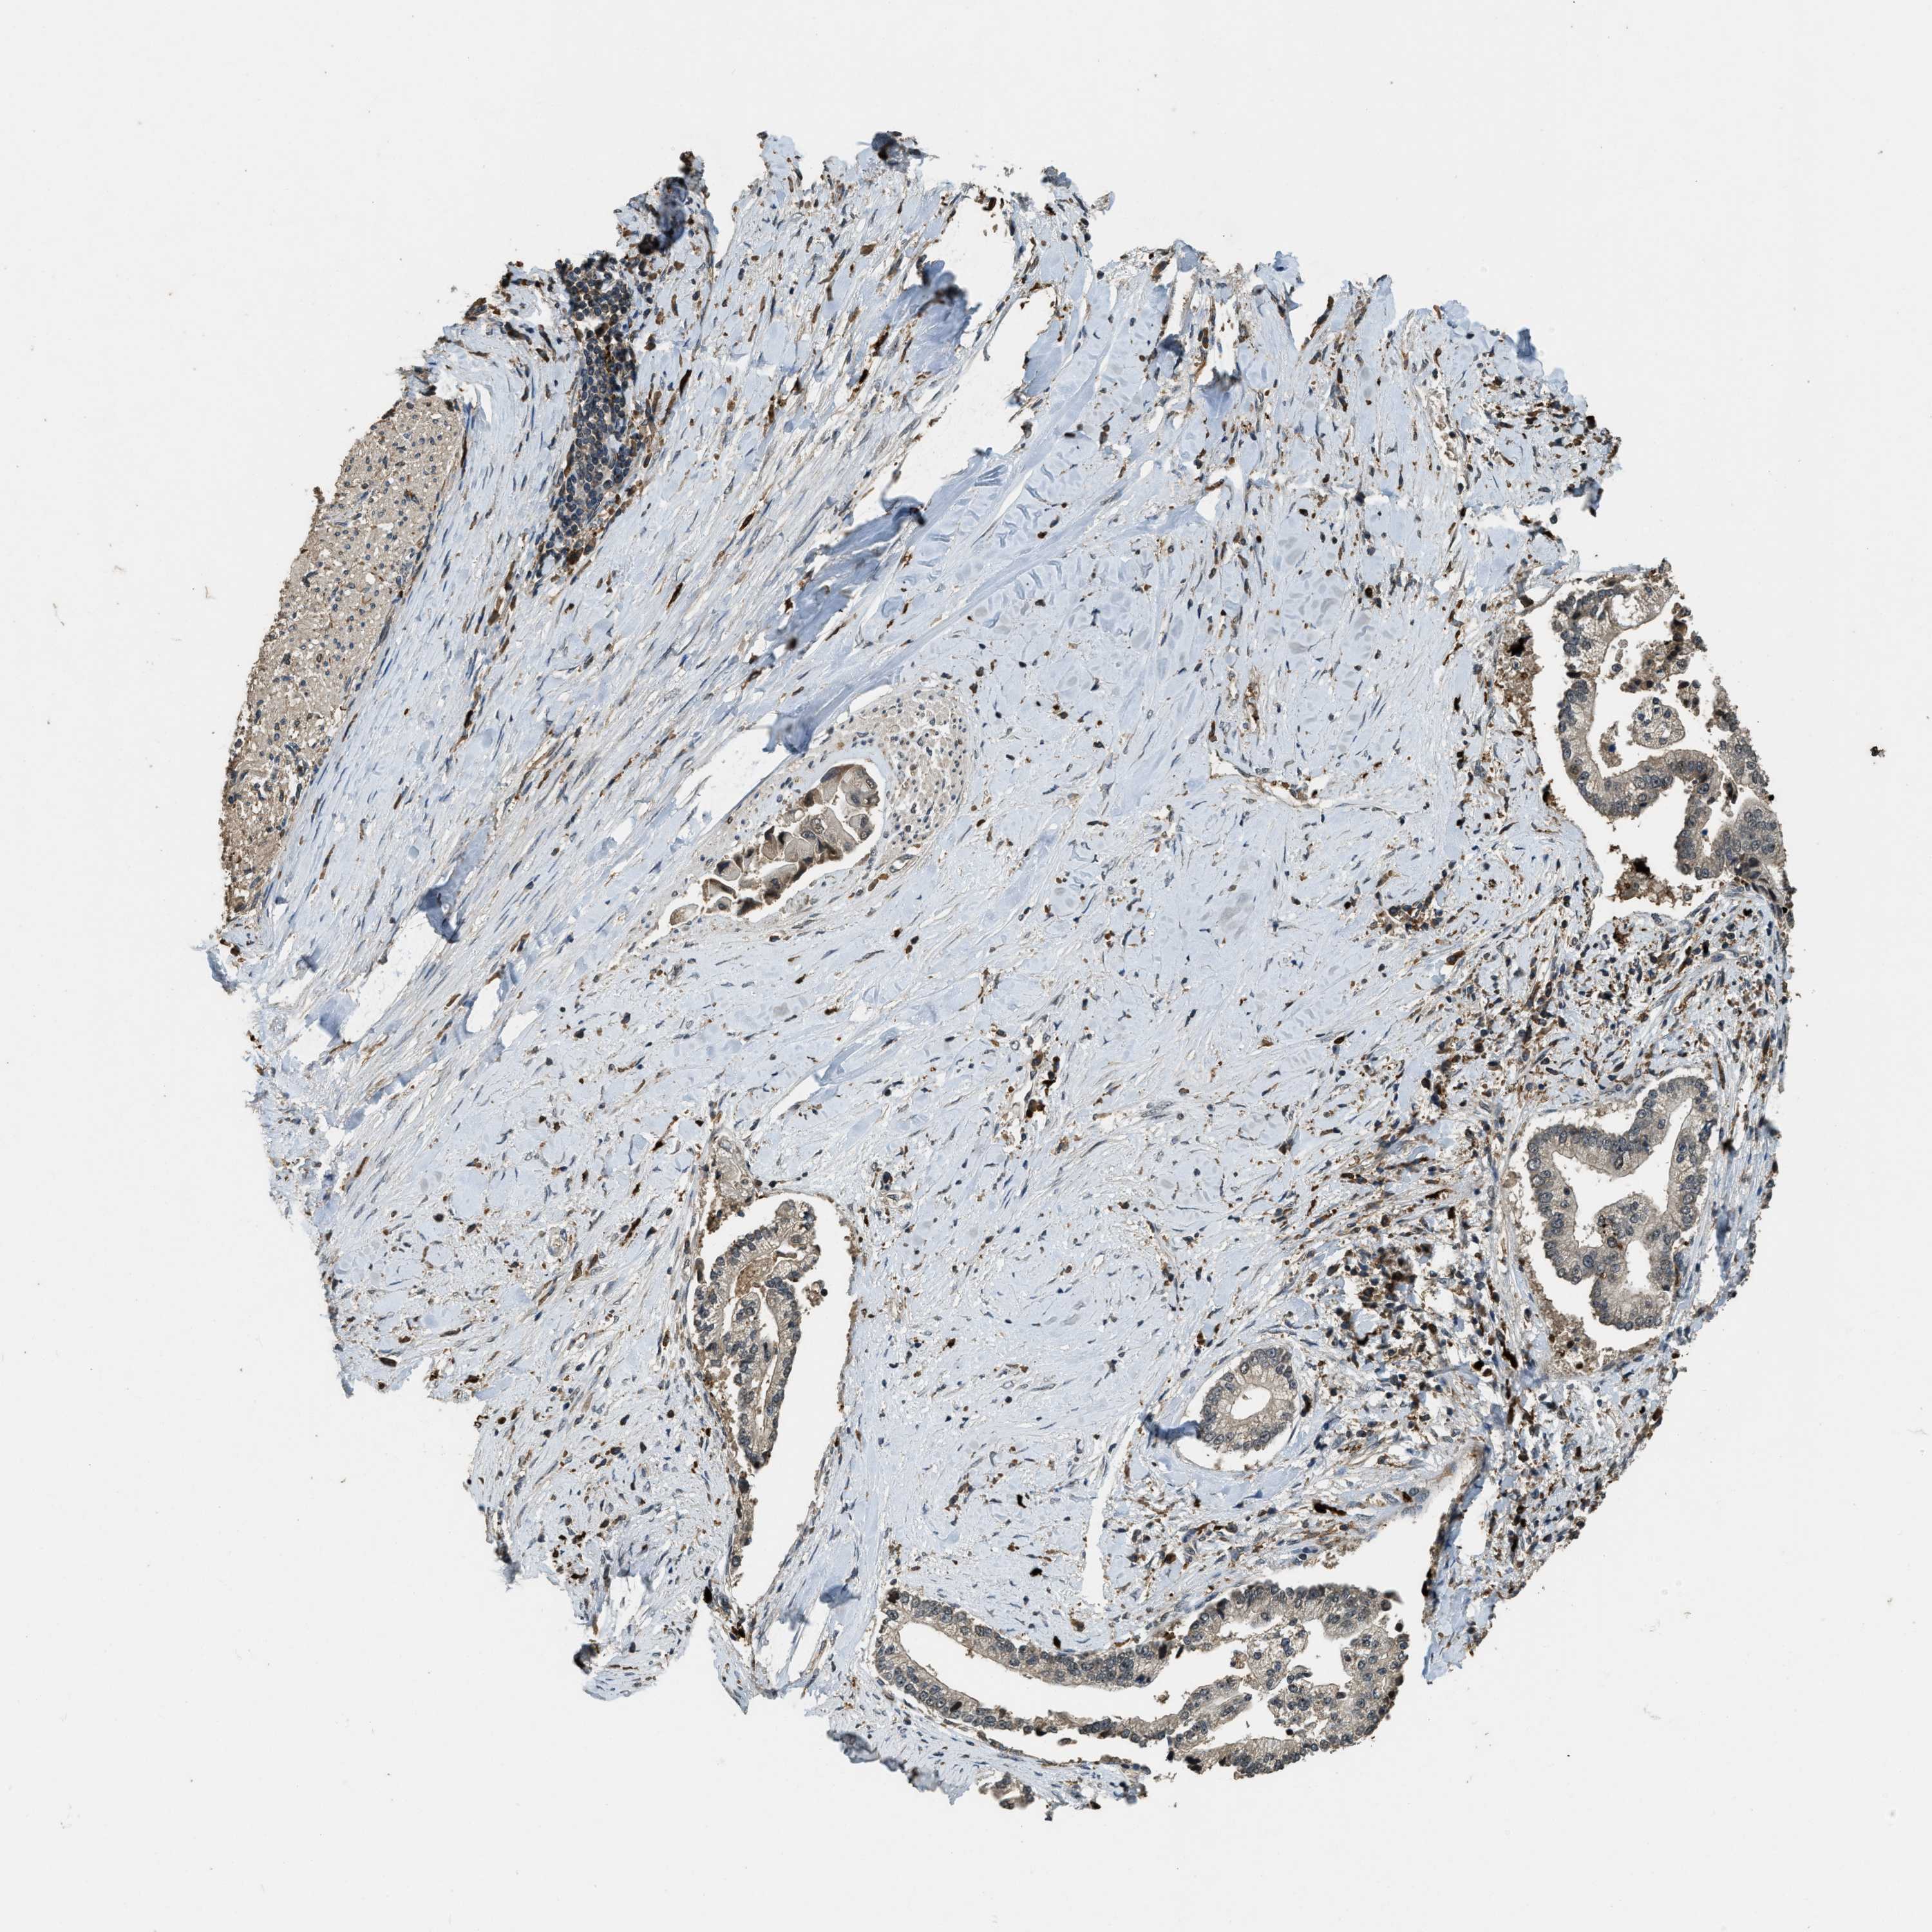

LIVER CANCER - Protein expressioni

A mouse-over function shows sample information and annotation data. Click on an image to view it in a full screen mode. Samples can be filtered based on level of antibody staining by selecting one or several of the following categories: high, medium, low and not detected. The assay and annotation is described here.

Note that samples used for immunohistochemistry by the Human Protein Atlas do not correspond to samples in the TCGA dataset.

Antibody stainingi

Antibody staining in the annotated cell types in the current human tissue is reported as not detected, low, medium, or high, based on conventional immunohistochemistry profiling in selected tissues. This score is based on the combination of the staining intensity and fraction of stained cells.

Each image is clickable and will lead to virtual microscopy that enables deeper exploration of all samples and also displays staining intensity scores, fraction scores and subcellular localization as well as patient and tissue information for each sample.

Antibody HPA018133

Staining

High

Medium

Low

Not detected

Intensity

Strong

Moderate

Weak

Negative

Quantity

>75%

75%-25%

<25%

None

Location

Nuclear

Cytoplasmic/membranous

Cytoplasmic/membranous,nuclear

Cholangiocarcinoma

Carcinoma, Hepatocellular, NOS